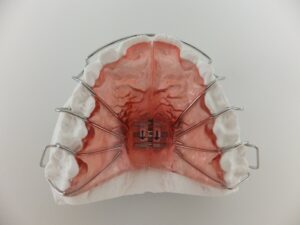

当院で使用している、上アゴの取り外し可能な装置です。

中心にねじが埋め込んであり、そのねじを回すことによって装置を広げます

ねじを回したときの装着感は「ちょっときつくなった感じ」です。

痛みはほとんどありません。

他にも、取り外さないタイプなどもあります。

これはワイヤーの力で顎を内側から広げます。

取り外し式の装置より歯ブラシを頑張らなくてはいけません。